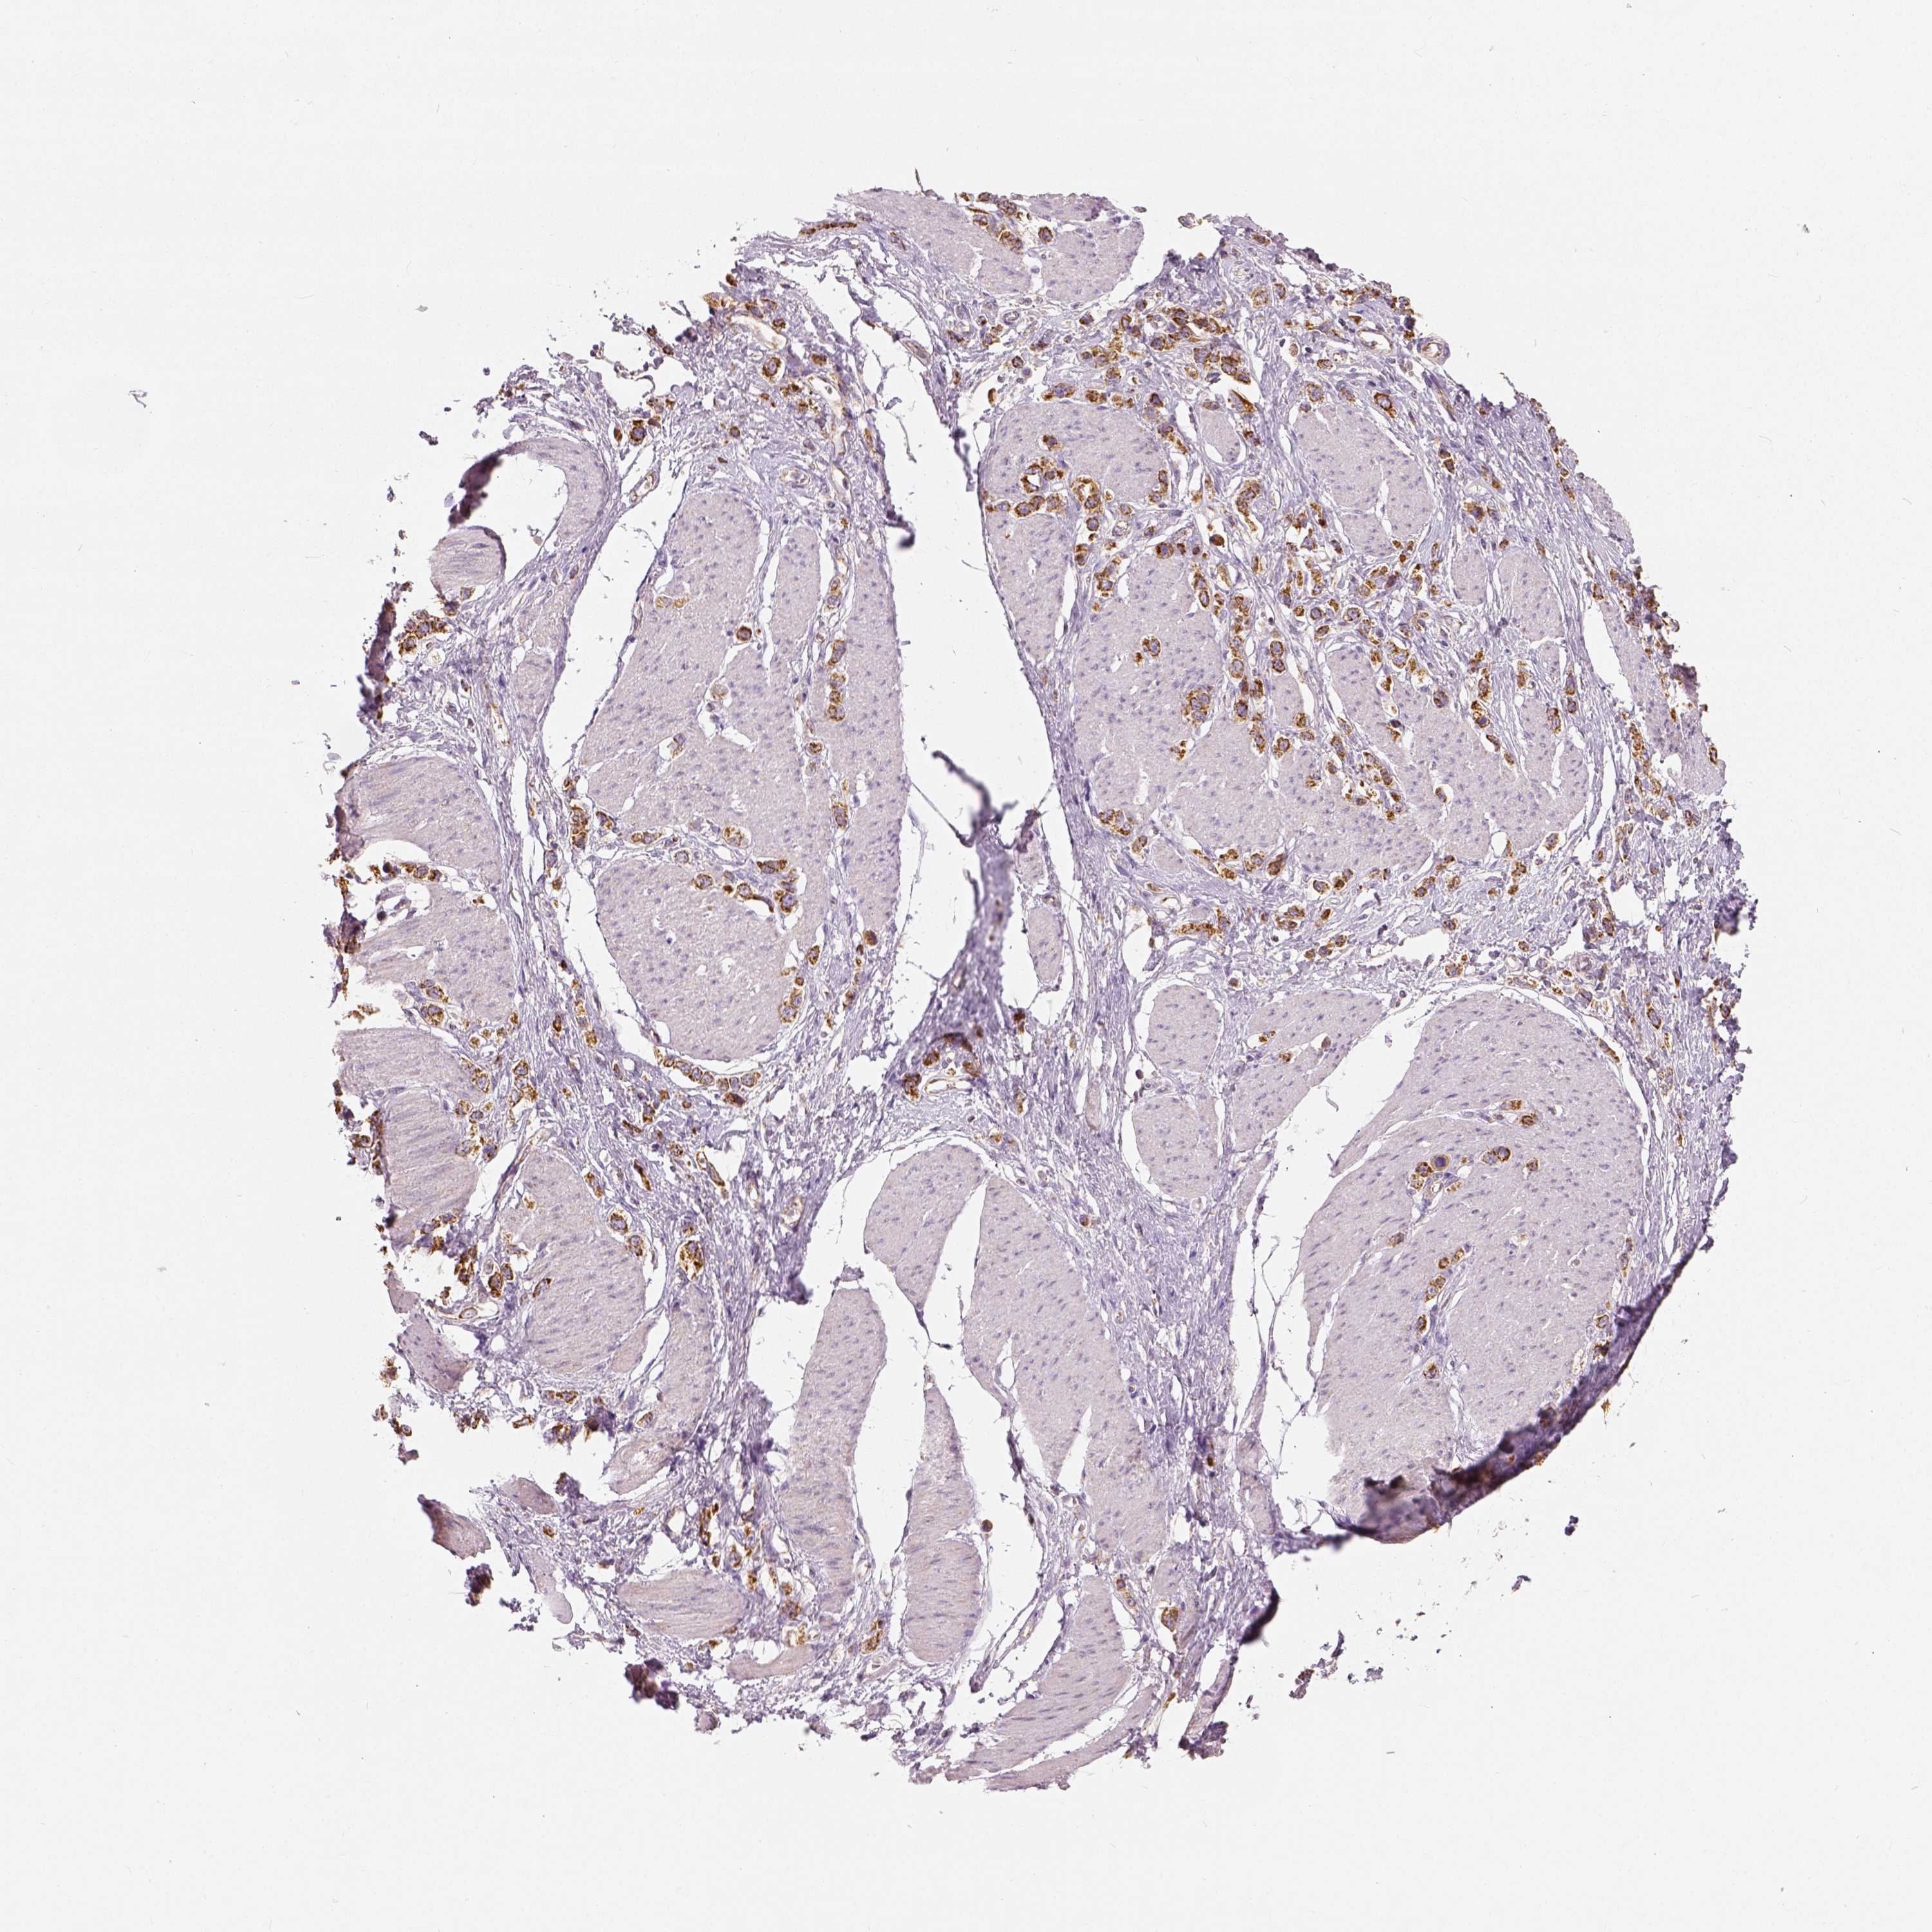

STOMACH CANCER - Protein expressioni

A mouse-over function shows sample information and annotation data. Click on an image to view it in a full screen mode. Samples can be filtered based on level of antibody staining by selecting one or several of the following categories: high, medium, low and not detected. The assay and annotation is described here.

Note that samples used for immunohistochemistry by the Human Protein Atlas do not correspond to samples in the TCGA dataset.

Antibody stainingi

Antibody staining in the annotated cell types in the current human tissue is reported as not detected, low, medium, or high, based on conventional immunohistochemistry profiling in selected tissues. This score is based on the combination of the staining intensity and fraction of stained cells.

Each image is clickable and will lead to virtual microscopy that enables deeper exploration of all samples and also displays staining intensity scores, fraction scores and subcellular localization as well as patient and tissue information for each sample.

Antibody HPA036978

Antibody HPA036979

Antibody CAB068215

Staining

High

Medium

Low

Not detected

Intensity

Strong

Moderate

Weak

Negative

Quantity

>75%

75%-25%

<25%

None

Location

Nuclear

Cytoplasmic/membranous

Cytoplasmic/membranous,nuclear

Adenocarcinoma, NOS